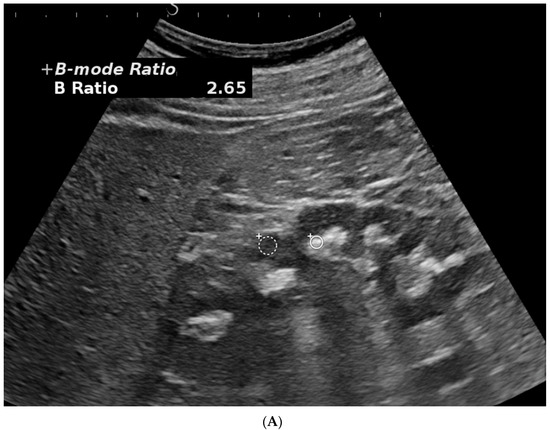

- Bardin, T.; Nguyen, Q.D.; Tran, K.M.; Le, N.H.; Do, M.D.; Richette, P.; Letavernier, E.; Correas, J.-M.; Resche-Rigon, M. A cross- sectional study of 502 patients found a diffuse hyperechoic kidney medulla pattern in patients with sereve gout. Kidney Int. 2021, 99, 218–226. [Google Scholar] [CrossRef]

- Bardin, T.; Tran, K.M.; Nguyen, Q.D.; Sarfati, M.; Richette, P.; Vo, N.T.; Bousson, V.; Correas, J.-M. Renal medulla in severe gout: Typical findings on ultrasonography and dual-energy CT study in two patients. Ann. Rheum. Dis. 2018, 78, 433–434. [Google Scholar] [CrossRef]